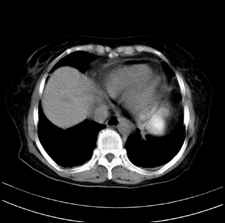

患者,女,75岁。腹痛,体黄5日,膝胸位时腹痛缓解。肝功能明日出来。彩超提示胆总管占位,未见血流信号。心电图提示s-t段改变。患者体质较弱,未能增强。

胆总管多发结石伴肝内外胆管轻度扩张。

胆总管上段,腔内有软组织密度影 ,ct值36-44hu。大家看有没有胆管癌的可能。

肝囊右.肾上腺囊肿

胆总管多发结石伴肝内外胆管扩张。